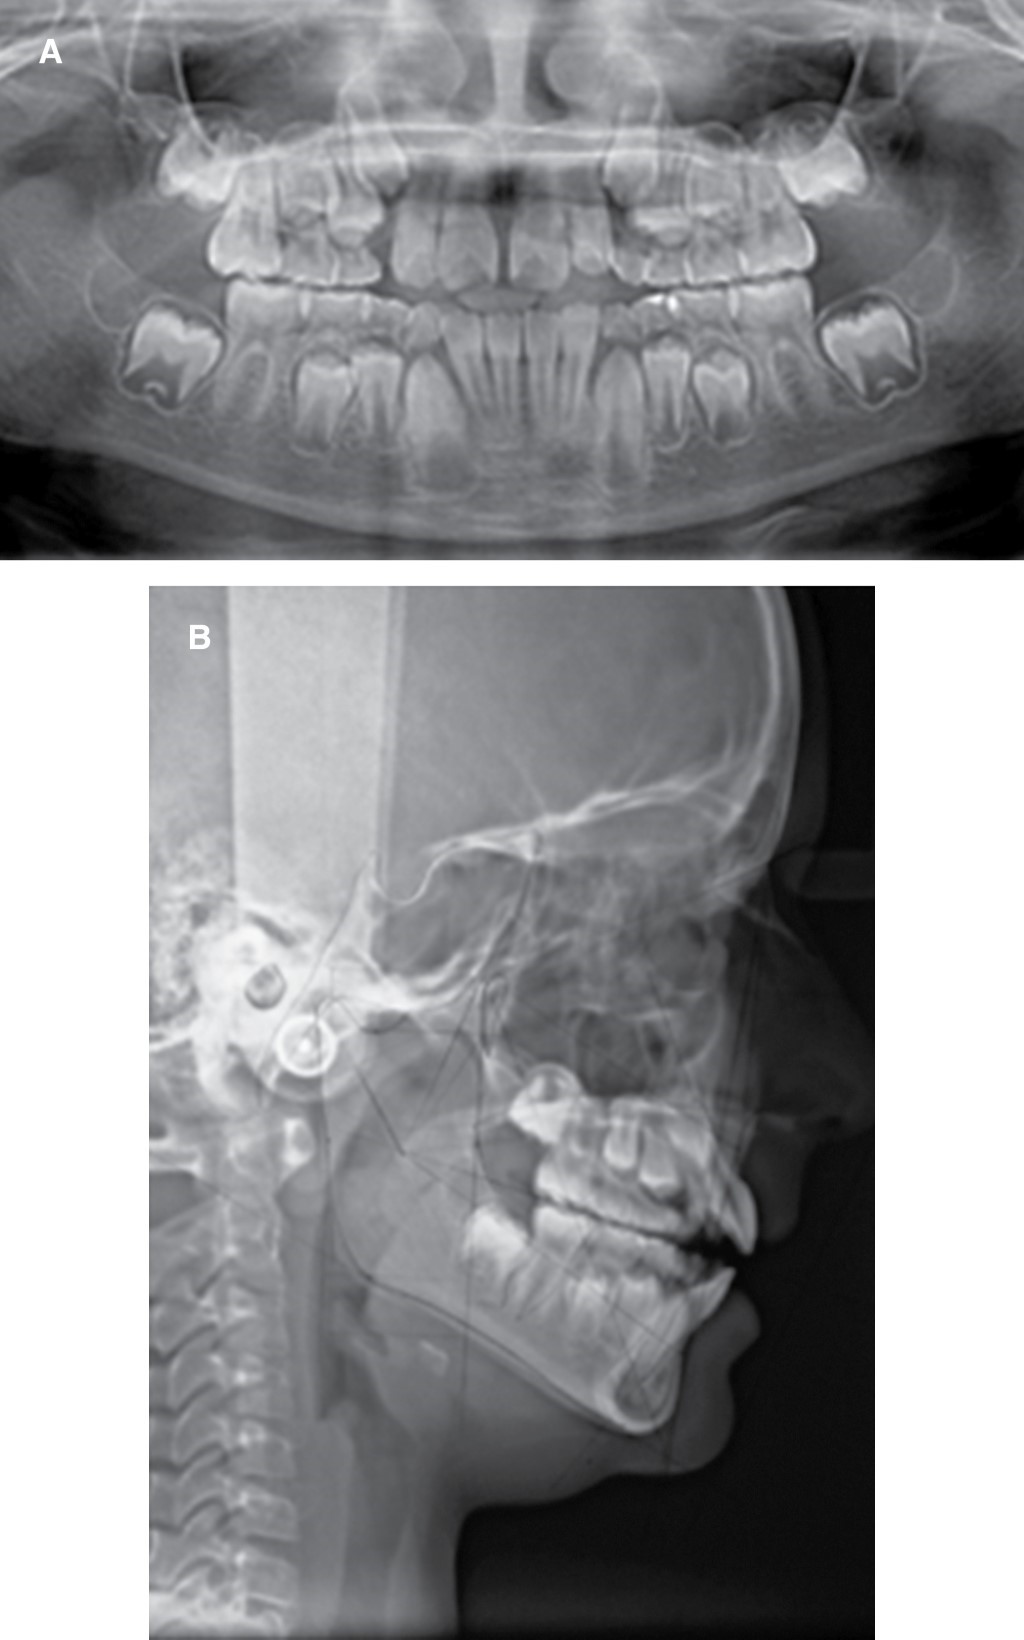

En la radiografía panorámica (Figura 3A) se observan dientes permanentes por erupcionar, cóndilos aparentemente sanos y vías aéreas ligeramente obstruidas.

Se diagnosticó como una clase II división 1 esqueletal con tendencia a clase III por hipoplasia del maxilar, compensando por una rotación mandibular en sentido de las manecillas del reloj, como se muestra en la Figura 3B y Tabla 1.

Figura 3